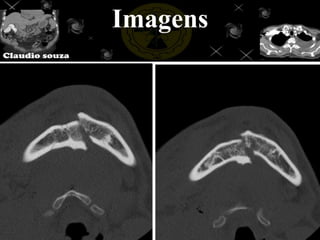

Imagens